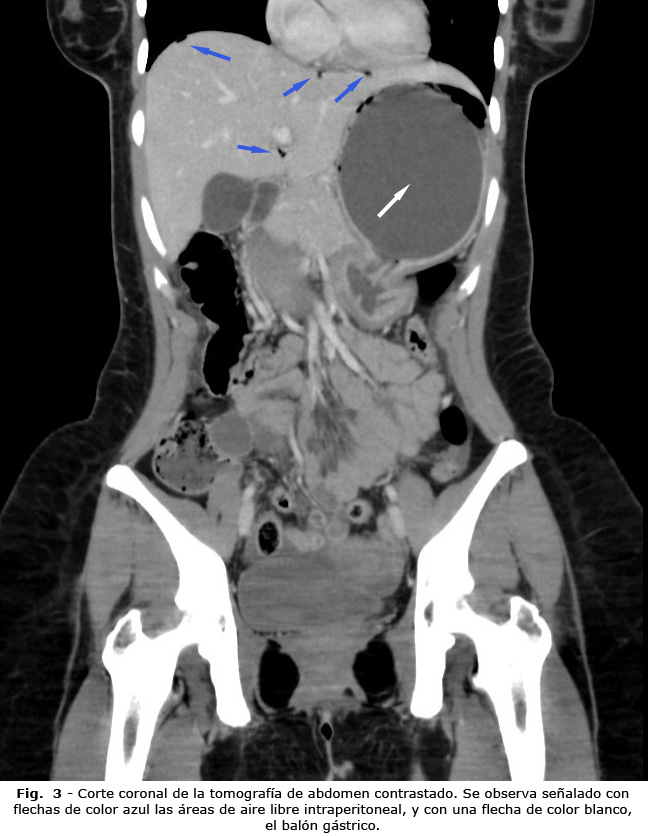

Ante la sospecha de posible perforación secundaria, se decidió solicitar radiografía toracoabdominal de pie, para evaluar la presencia de neumoperitoneo. Se realizó radiografía del tórax en la cual se evidenció neumoperitoneo subdiafragmático derecho reducido (Fig. 1). Se procedió a realizar tomografía axial computarizada (TAC) contrastada de abdomen, que reportó signos que sugerían perforación gástrica (engrosamiento de las paredes del estómago, asociado a neumatosis de la pared y aire libre intraperitoneal) (Fig. 2 y Fig. 3), asociados a cambios inflamatorios intraperitoneales.